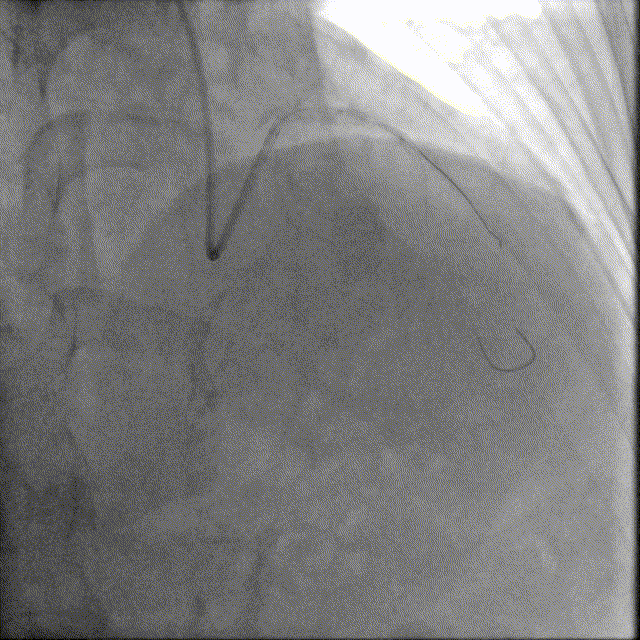

于前降支中段近段口串联2.5mm×18mm、3.0mm×18mm DES。

前降支开口精确定位植入3.5mm×18mm DES。

2.5mm-3.5mm后扩球囊后扩张。

最终结果满意,复查IVUS支架膨胀、贴壁良好!